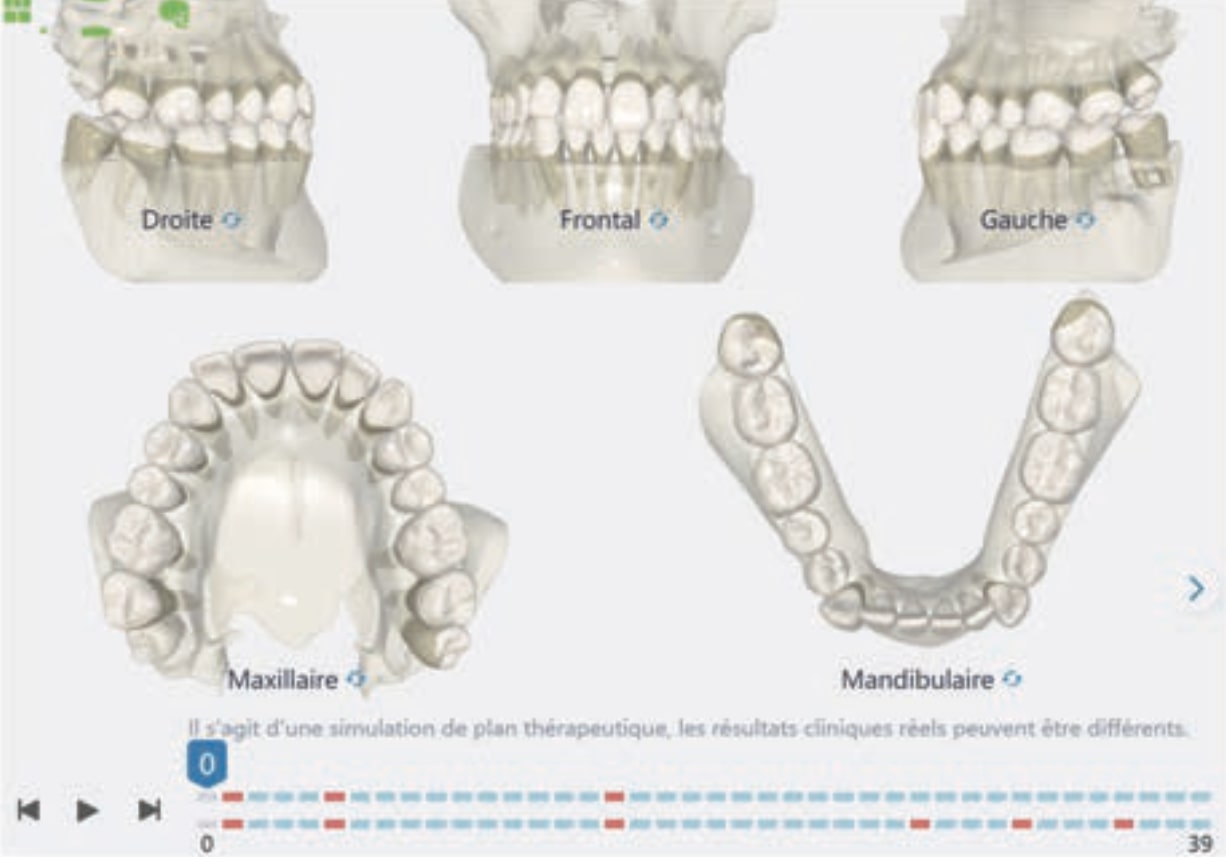

Treatment setup

Number of aligners: 39

• Distalization of the Third and Fourth Quadrants: Move the teeth distally in these quadrants to achieve a Class I relationship using the A8 protocol, improving the patient’s dental alignment and occlusion.

• Solve the Crossbite of Tooth 33: Correct the position of tooth 33 to eliminate the crossbite, contributing to a more balanced occlusion.

• Intrusion of the Lower Anterior Teeth: Adjust the vertical position of the lower anterior teeth to level the curve of Spee, improving the harmony of the occlusion.

• Improve the Root Position of Teeth 33 and 43: Optimize the position of the roots of teeth 33 and 43 in relation to the cortical bone to ensure adequate bone support and long-term stability.